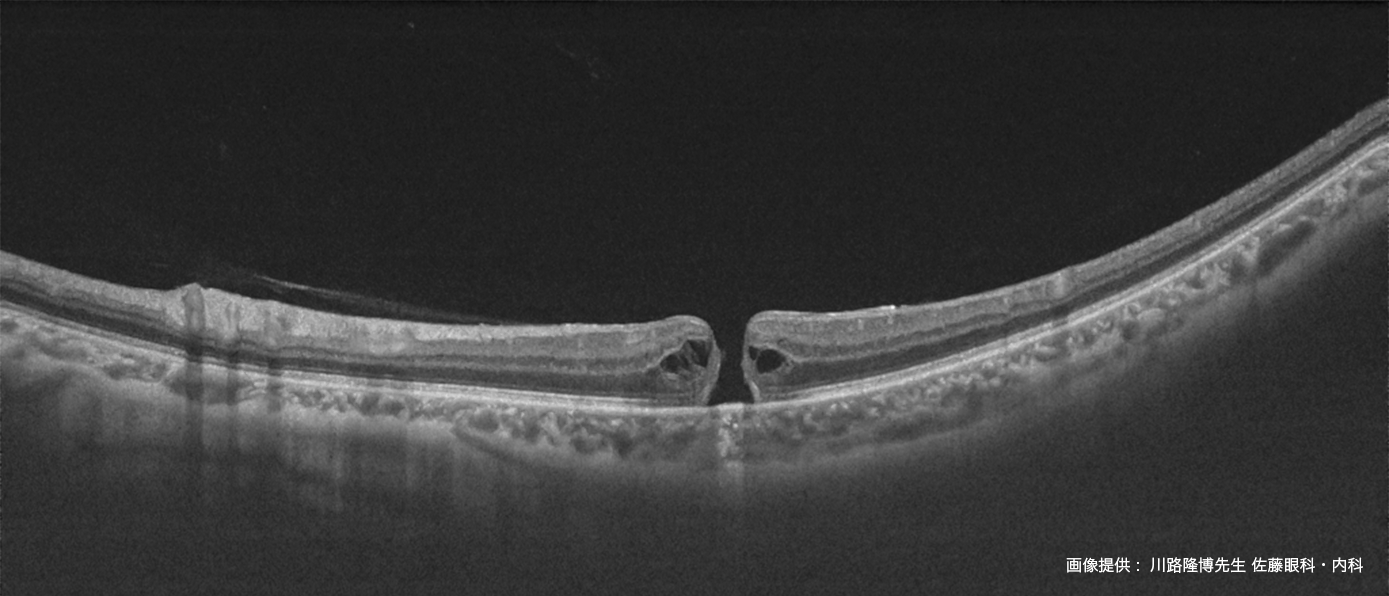

信頼性の高いSwept-Source OCTは12mmの広範囲撮影において

デノイズ効果を発揮し、さらに見やすい画像を提供します。

診断に有用な撮影機能を集約 - 白内障や硝子体混濁のある疾患眼に対しても鮮明なOCT 像を表示

DRI OCT Triton シリーズにトプコン独自のアルゴリズムOCT Angiography Ratio Analysis = OCTARA™を搭載したことで、

脈絡膜レベルの血流まで高感度、高侵達に画像化します¹。トプコン独自のアルゴリズムOCTARA は、

同じ断面で撮影された複数のOCT 画像から血管内の血流の様子を画像化する技術です。弱い信号変化でも高感度で画像化できるため、

毛細血管の観察など臨床に活用されています。